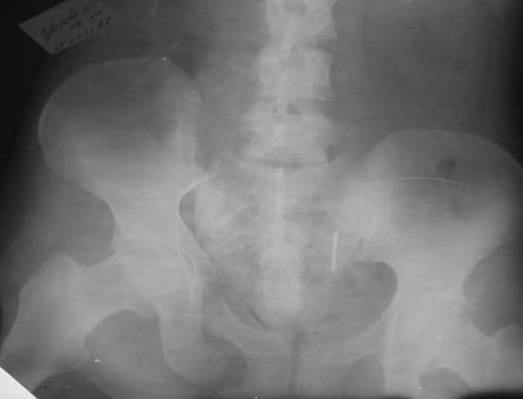

Пациентка С.26 лет. Травма за 6 месяцев до поступления

Укорочение правой нижней конечности до 10см